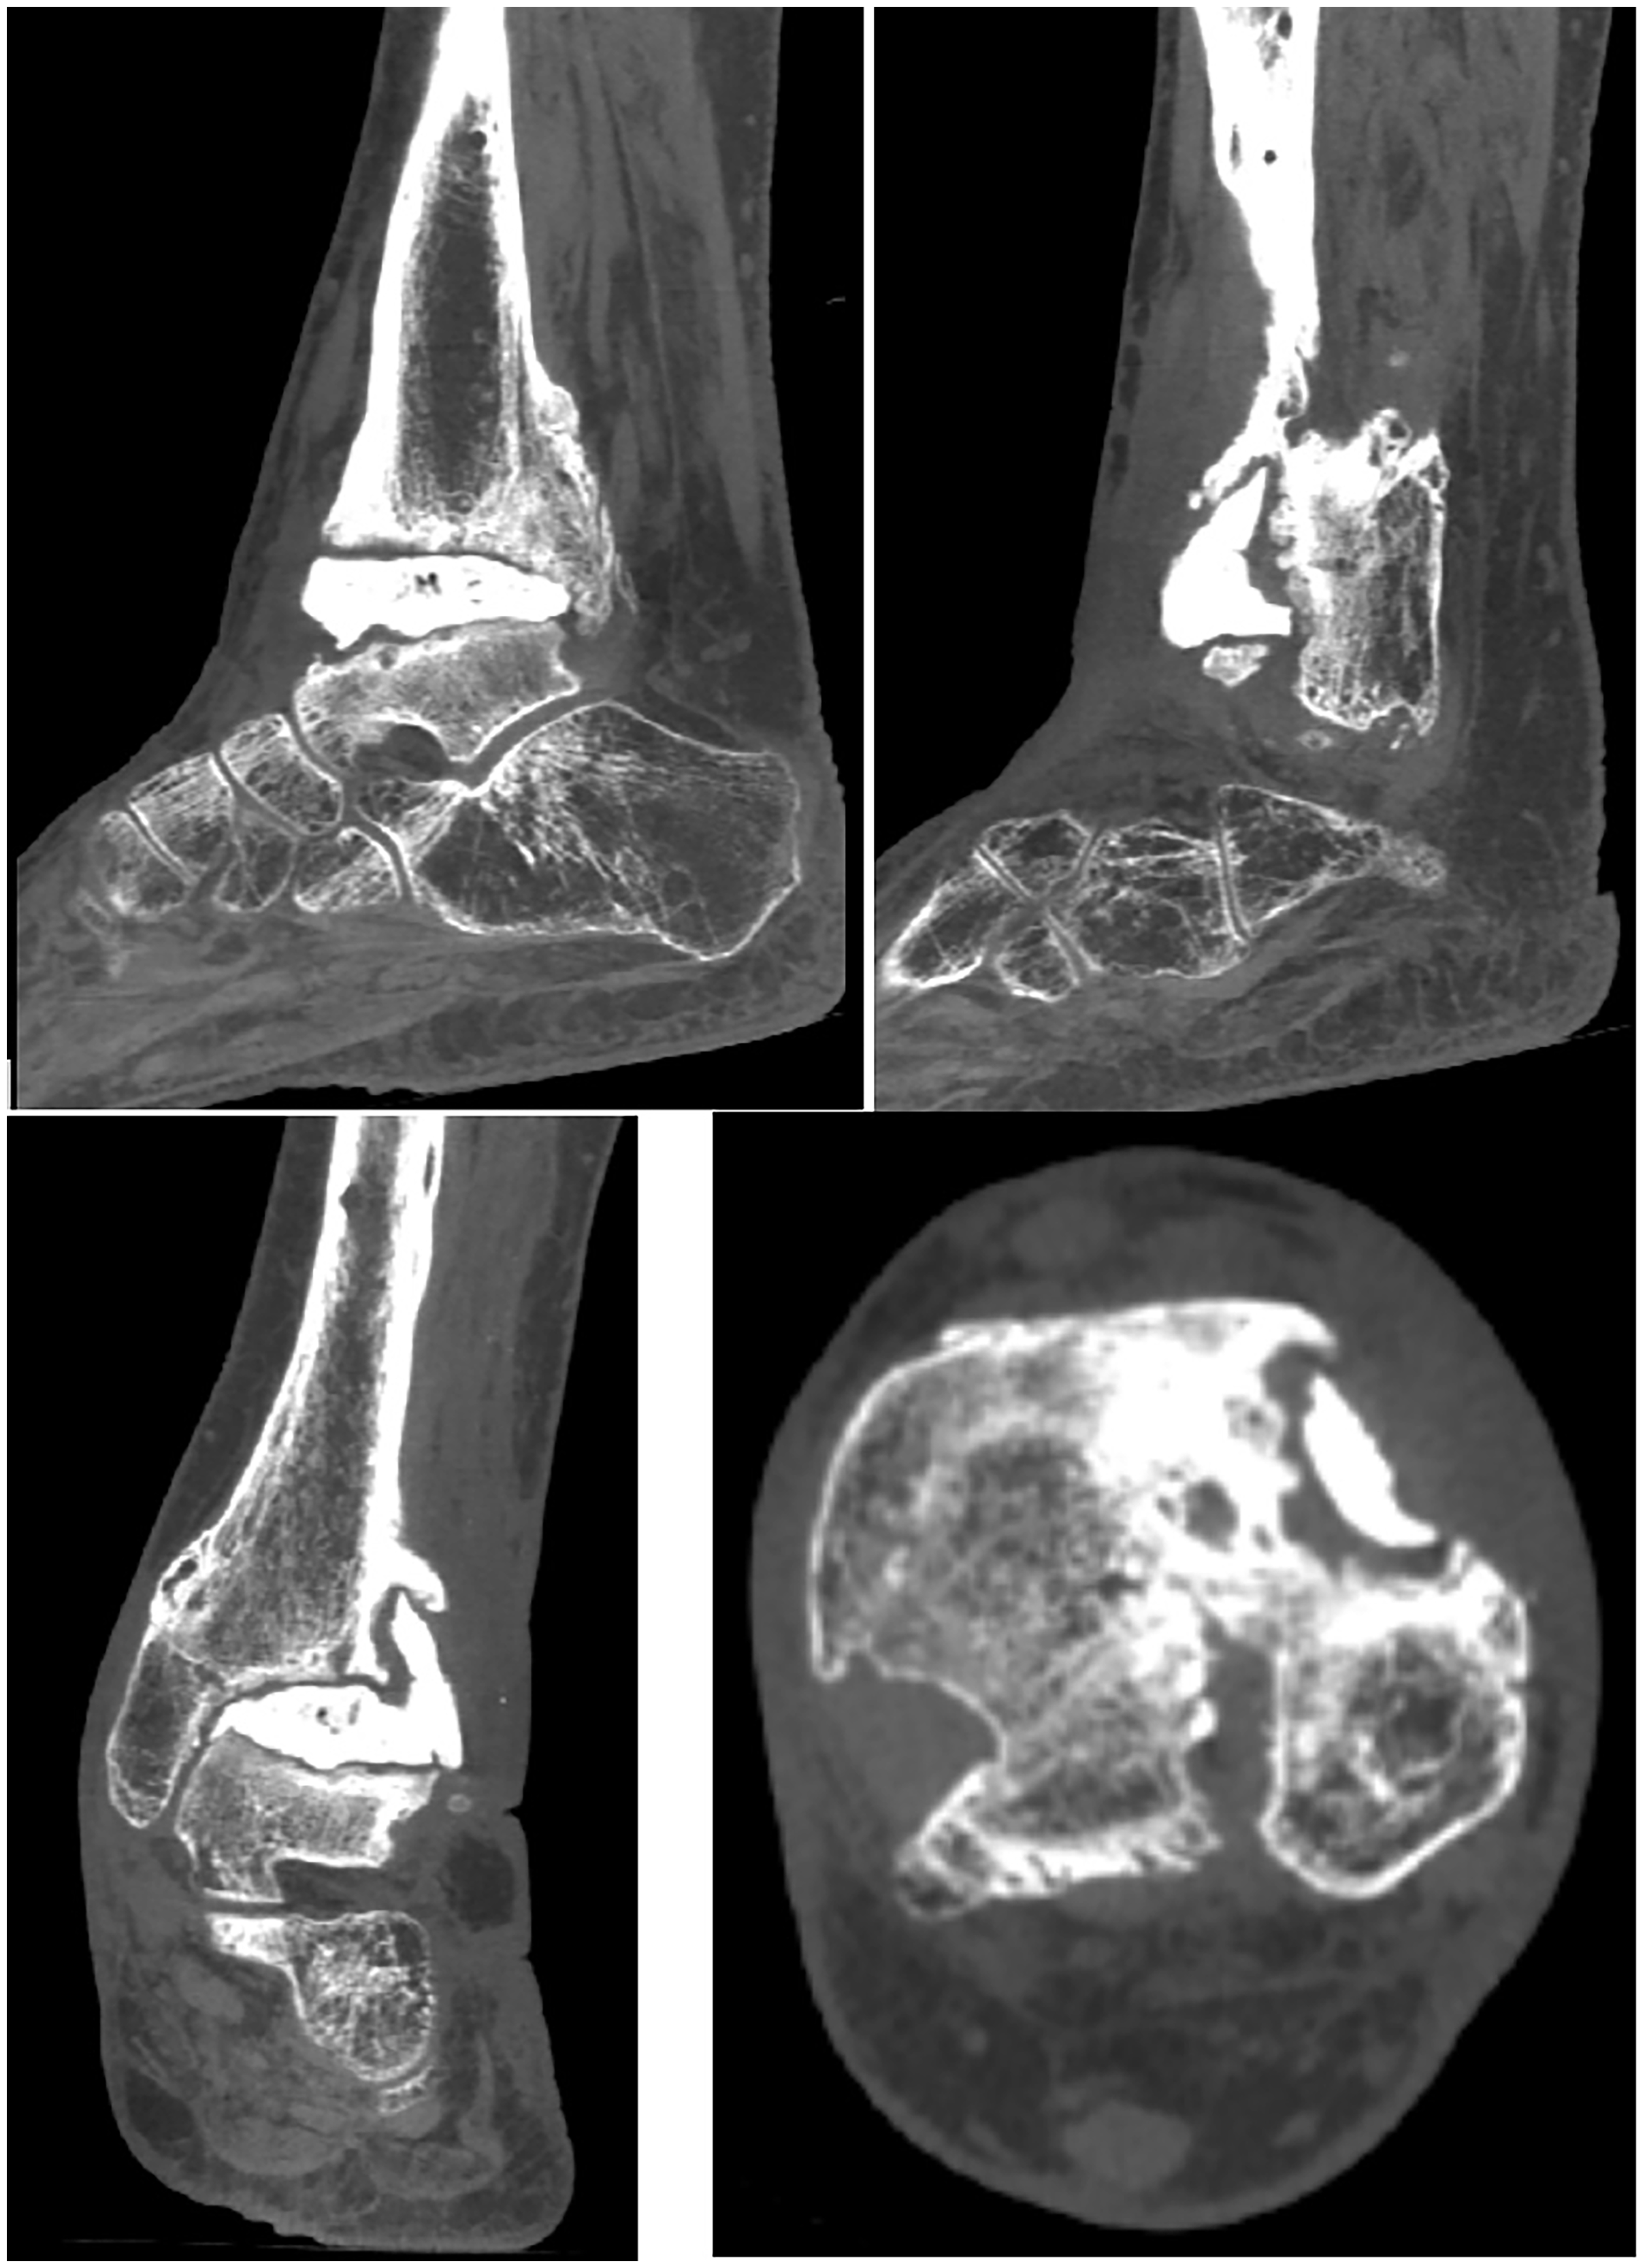

Postoperatively, surgical soft-tissue and bone cultures grew Enterobacter cloacae, for which infectious disease placed the patient on 1 g ertapenem IV daily for 6 weeks. The wound to the anterolateral ankle re-epithelialized 1.5 months postoperatively with negative pressure wound therapy followed by saline wet-to-dry dressing changes. She remained nonweightbearing for 6 weeks and progressed to a controlled ankle motion boot with protective weightbearing at week 7. Based on stable radiographs without migration or extrusion of the antibiotic spacer, she was transitioned to an ankle-foot orthosis 3 months postoperatively as an alternative to a septic fusion. Based on her age, functional activity, and morbidity associated with two-stage surgery, if the interpositional arthroplasty remained stable, long-term functional bracing was deemed reasonable. At 12 months, a computed tomography scan was ordered, confirming a stable prosthesis with the anterior syndesmotic “fin” extending 25 mm proximal to the syndesmotic articulation (Fig. 5). The patient maintains a functional, plantigrade foot with adequate ankle range of motion for gait 16 months postoperatively (Fig. 6).

Figure 6. Postoperative computed tomography scan illustrating a stable PMMA-AEC spacer without evidence of migration or extrusion. The anterior “fin” extends 25 mm proximally into the tibiofibular syndesmotic articulation.